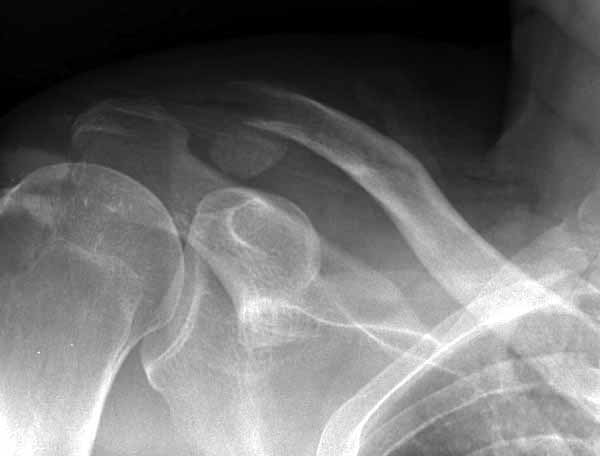

Из заданного вопроса в этом посте я понял, что разговор идет по поводу “методики применения ключичной пластины с крючком при акромиальных переломах”, т.е не ведется разговор “по поводу лечения косых переломов ключицы”.

Если так, тогда Юрий прав, методов лечения акромиона пластинами нельзя было найти. Обычно изобретали из реконструкционных пластин 2.7 или 2.4 мм толщиной. Такая фиксация адекватно удерживает перелом акромиона. Только недавно компания Acumed создала пластину для переломов акромиона, здесь линк: http://www.acumed.net/sites/default/files/literature/brochure-surgical-technique/CPS00-11-A.pdf.

По поводу пластины с крючком, Ваше заключение "не вижу препятствий для фиксации акромиального косого перелома ключицы для МОС использовать пластинку с крючком" вызывает сомнение.

Предназначенную для лечения повреждений связочного аппарата акромиально-ключичного сочленения пластину можно применить не при всех переломах акромиального конца ключицы. Потому что имплант рассчитан на интактную ключицу и не для переломов ключицы. Пластина короткая, не покрывает медиальный диафизарный фрагмент ключицы и за счет тракции стерноклеидомастоидеус такая фиксация прорвется через несколько дней.